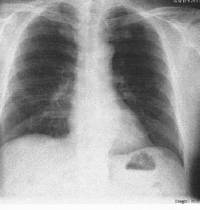

図1 クリックで拡大

図1の補足

沼田自身の胸のレントゲン写真です。

何だか恥ずかしいですが・・・・

上の図1と同じである事が確認できると思います。

多少の違いは人それぞれ顔が違うように身体の内部もちがいます。

黒い部分が肺で、鎖骨の上まで肺があります。